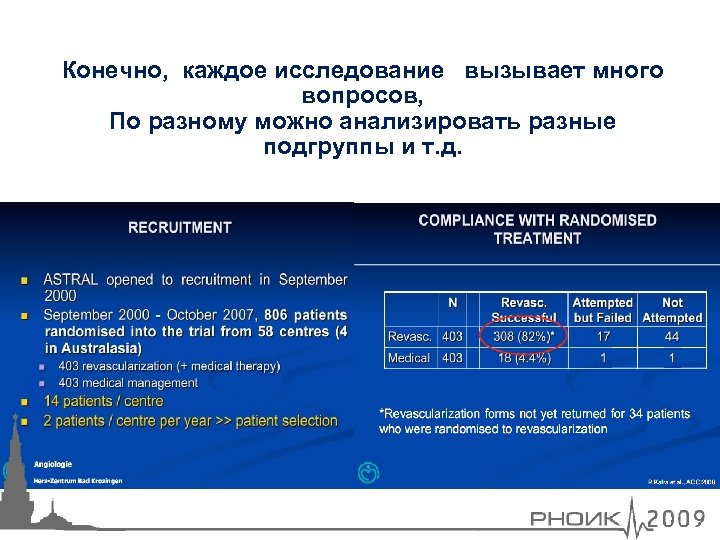

Конечно, каждое исследование вызывает много вопросов, По разному можно анализировать разные подгруппы и т. д.

Конечно, каждое исследование вызывает много вопросов, По разному можно анализировать разные подгруппы и т. д.